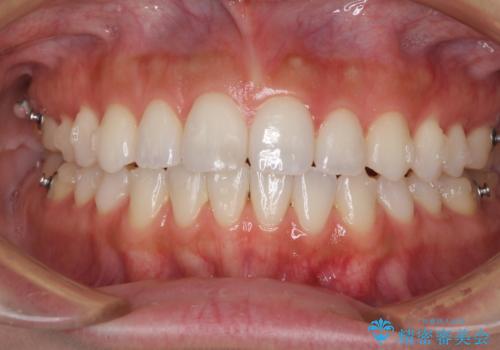

前歯のオープンバイトを治したい インビザラインでの矯正治療

- 前歯の上下スペースによる話しにくさと顎への負担を気にして来院された患者様です。

インビザラインにより上顎の大臼歯を圧下し、上下の前歯の隙間を閉じていくこととしました。

上顎の奥歯を圧下させることで、上下前歯を接触させるように計画しました。

前歯が急に接触するようになり、慣れるまで時間がかかりましたが、前歯でものが咬めるようにもなり、患者様には大変満足していただきました。